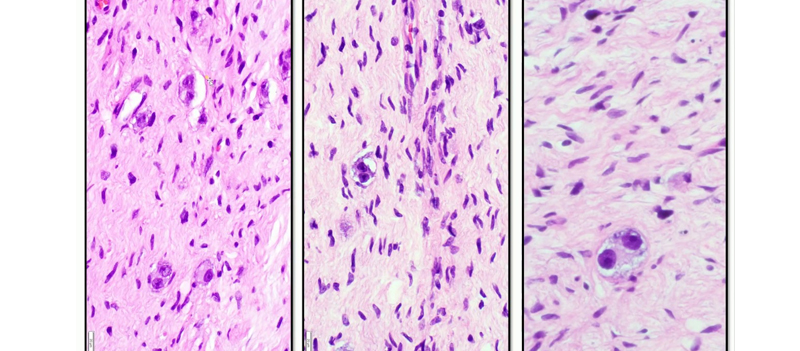

Neuroblastoma & Ganglioneuroma

Neuroblastoma

Ganglioneuroma

Ganglioneuroma is a tumor of the autonomic nervous system.